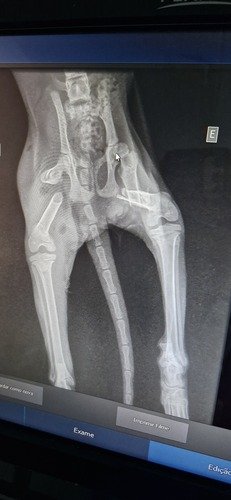

Oi, pessoal… 💔🐾Venho aqui com o coração apertado pedir ajuda pra salvar a vida da Luna Guerreira.Eu encontrei a Luna na rua e, infelizmente, presenciei uma cena muito triste… Ela foi atropelada e, logo em seguida, atacada por três cães. Foi desesperador ver tudo aquilo acontecer e não fazer nada não era uma opção. Naquele momento, decidi resgatar ela.A Luna sofreu muito… ela teve várias fraturas nas patas traseiras e ainda um prolapso retal. Mesmo com tanta dor, ela continua lutando, mostrando uma força incrível — por isso o nome: Luna Guerreira.Ela precisa passar por uma cirurgia URGENTE para sobreviver. O custo total, incluindo cirurgia, internação, medicamentos e cuidados, gira em torno de R$ 4.500,00. Infelizmente, eu não tenho condições de arcar com tudo isso sozinho.Estou criando essa vakinha com toda humildade pra pedir ajuda. Qualquer valor, por menor que seja, já faz muita diferença pra dar uma chance de vida pra Luna.Se você não puder contribuir financeiramente, peço de coração que compartilhe essa história. Isso já ajuda muito a alcançar mais pessoas.A Luna já sofreu demais… agora ela precisa de uma chance pra viver, sem dor, com dignidade e amor.Desde já, agradeço de coração a todos que puderem ajudar 🙏🐱💕Muito obrigado.